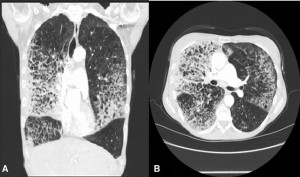

- Chụp cắt lớp vi tính mạch máu phổi (CTPA): Đây là phương pháp chẩn đoán hình ảnh được ưu tiên hàng đầu do có độ nhạy và độ đặc hiệu cao đối với thuyên tắc phổi. Tuy nhiên, xét nghiệm này cần sử dụng thuốc cản quang tiêm tĩnh mạch nên có thể không phù hợp với người bị bệnh thận. Nếu không thể thực hiện CTPA, bác sĩ có thể chỉ định xạ hình thông khí/tưới máu (VQ scan).

Chụp cắt lớp vi tính (Chụp CT) là phương pháp chẩn đoán hình ảnh tiêu chuẩn được sử dụng phổ biến nếu bác sĩ nghi ngờ bạn bị thuyên tắc phổi (PE).